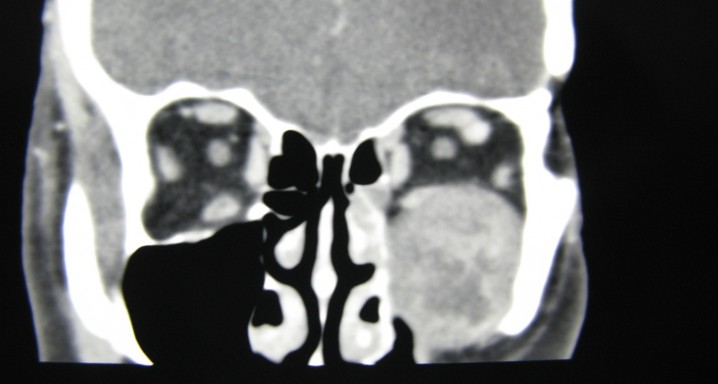

Los tumores orbitarios también pueden dividirse en benignos y cancerosos, siendo los primeros más frecuentes. Algunos tumores orbitarios, pese a ser benignos, como el hemangioma cavernoso, pueden entrañar problemas visuales debido a su localización orbitaria. Las lesiones cancerosas de la órbita son poco frecuentes, y entre ellas la más frecuente es el linfoma orbitario, que suele tener un buen pronóstico de curación. Otros tumores que pueden presentarse en esta área son los de la glándula lagrimal o las metástasis de otros cánceres.